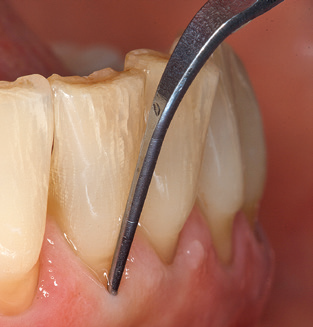

The current working concept for SPT

Fig. 4: Flexible probes with millimetre markings are recommended for the probing of dental implants (e.g. Colorvue Kit PCV11KIT6, Hu­Friedy). – Fig. 5a and b: A straight working tip (1P, W&H Dentalwerk Bürmoos GmbH) is a suitable instrument for use on all natural teeth. – Fig. 6: Curved working tips (3Pr/3Pl, W&H Dentalwerk Bürmoos GmbH) lend themselves to the processing of difficult-to-reach areas of the tooth and root surfaces (e.g. furcations). – Fig. 7: The tapered, hexagonal implant cleaning tip (1I, W&H Dentalwerk Bürmoos GmbH) permits atraumatic and efficient cleaning of the crown and abutment surfaces. – Fig. 8: Titanium and carbon curettes are suitable instruments for the manual cleaning of the implant surfaces.

Good illumination of the working field facilitates the process considerably. The system used by the authors achieves this thanks to a 5x LED ring integrated in the handpiece. Naturally, a range of working tips for different indications is also offered. A straight, universally employable tip is the basic instrument required for machine cleaning of natural teeth (Fig. 5a and b). Curved tips, which allow access to exposed furcations, are also available for hard-to-reach areas in the posterior region (Fig. 6).